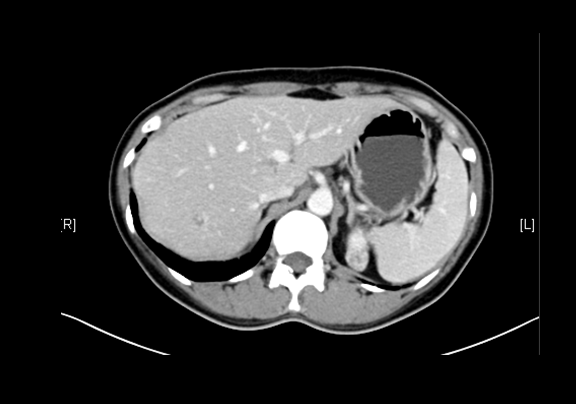

上腹部增强CT示:肝右叶海绵状血管瘤可能性大;肝囊肿;左肾上极肿瘤可能性大;双肾多发囊肿。

术前CT检查:

静脉期